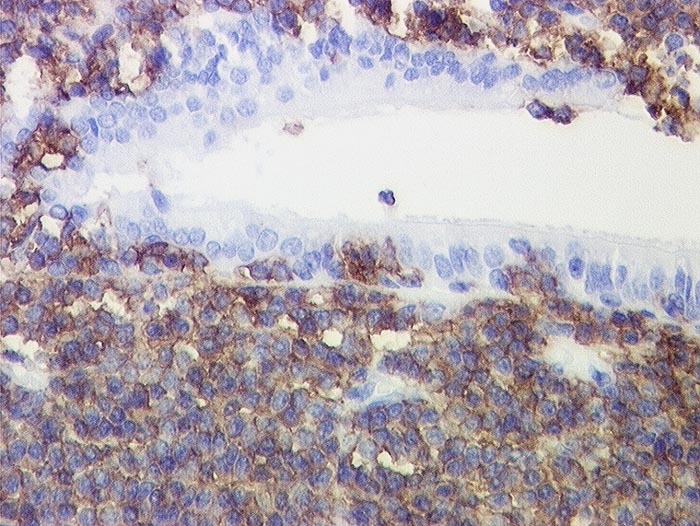

CD20

- Anfärbung:

- Zellmembran

- Reaktion im Normalgewebe:

- Pan B-Zell Marker positiv in allen B Lymphozyten, negativ in Plasmazellen.

- Reaktion in Neoplasien:

- Die meisten B-Zell Lymphome, etwa 50% der B Zell lymphoblastischen Lymphome und einige Myelome reagieren positiv.

- Diagnostischer Nutzen:

- Unterscheidung von reaktiven und neoplastischen Infiltraten zusammen mit CD3. Reaktive Infiltrate bestehen meist aus einem Gemisch von B und T Lymphozyten mit Überwiegen der T Lymphozyten. In B-Zell Lymphomen überwiegen CD20 positive B-Zellen.

Unterscheidung von B- und T-Zell Lymphomen.